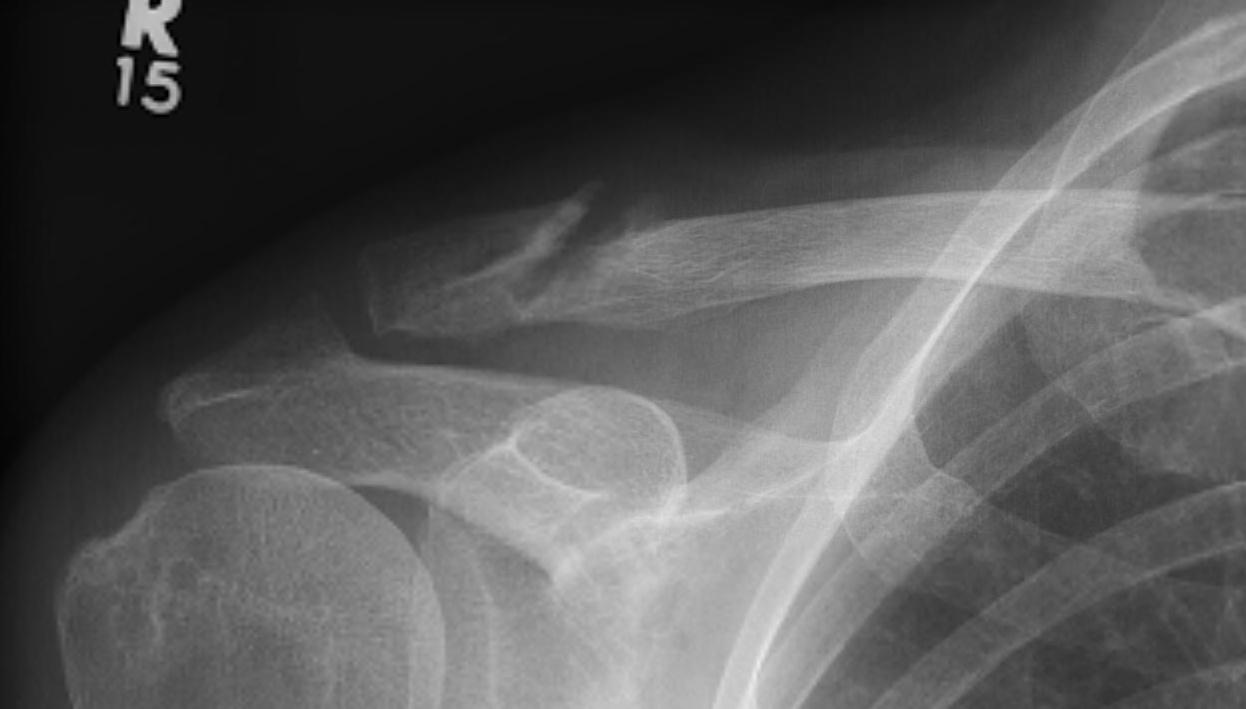

Neer Classification

Fracture lateral to the CC ligaments Non displaced

Fracture medial to the CC ligaments CCL ligaments attached to lateral fragment Medial fragment displaced superiorly |

Between conoid and trapezoid Conoid disrupted Trapezoid remains attached to the lateral fragment |

Lateral to CC ligaments Intra-articular extension Stable |

Periosteal sleeve disruption Pediatric Medial fragment displaced |

Comminuted Type II Medial fragment displaced |

Type I

Type II

Type V